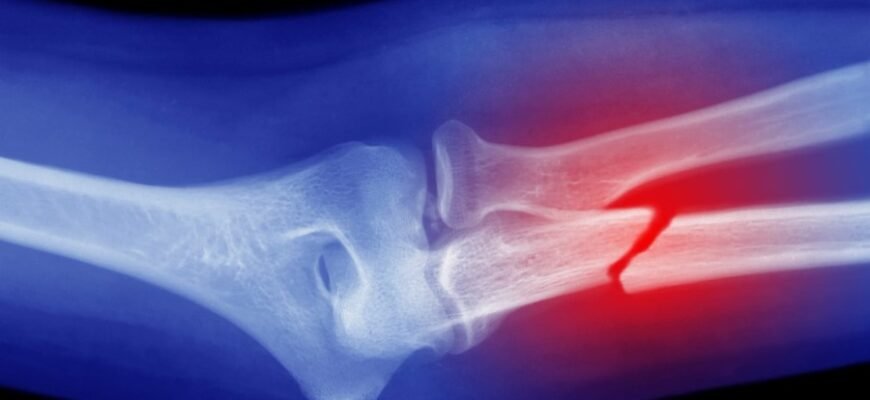

Як лікарі визначають перелом

Зараз медицина може все. Рентген — класика, але якщо складно — КТ, МРТ поруч. Лікар оглядає, оцінює рухи, реакцію на біль, форму кінцівки. Важливо: не лише виявити перелом, а зрозуміти його природу. Це не просто №1, це важливо для лікування. Операція чи гіпс? Все залежить. Але головне — повернути кістці її силу і форму. Без цього — ніяк.